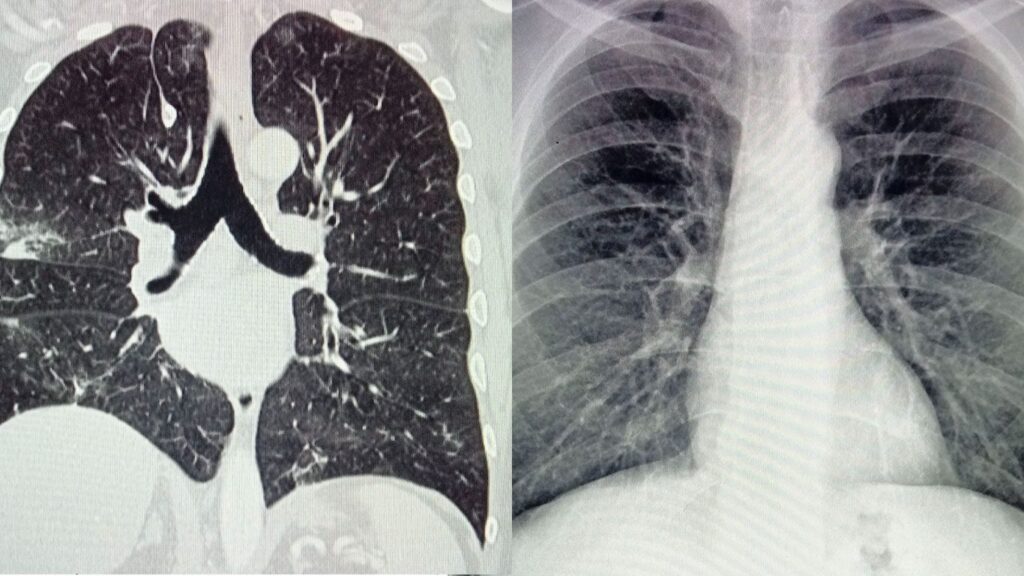

Asimismo, la compañía destacó que una de las razones de su alta letalidad es que la mayoría de los casos se diagnostican en etapas avanzadas, cuando los síntomas -como tos persistente, dolor torácico o falta de aire- ya están presentes y las opciones de tratamiento son limitadas.

En cuanto al cáncer de pulmón -que se divide en dos tipos, el de células pequeñas (CPCP) y el de células no pequeñas (CPCNP)-, explicó que existen comportamientos y tratamientos diferentes para ambos.

El CPCP representa cerca del 15 % de los casos a nivel mundial, es más agresivo y suele presentarse en personas con historial prolongado de tabaquismo. En México, su tasa de supervivencia a cinco años es de apenas un 5 %.

Por otra parte, el CPCNP agrupa varios tipos de cáncer epitelial, como el carcinoma de células escamosas, de células grandes y el adenocarcinoma; además, está asociado al tabaquismo, aunque también puede afectar a personas que nunca fumaron.

En específico, la biofarmacéutica señaló que el cáncer pulmonar en etapas tempranas puede tratarse mediante cirugía o radioterapia, lo que mejora significativamente la supervivencia.